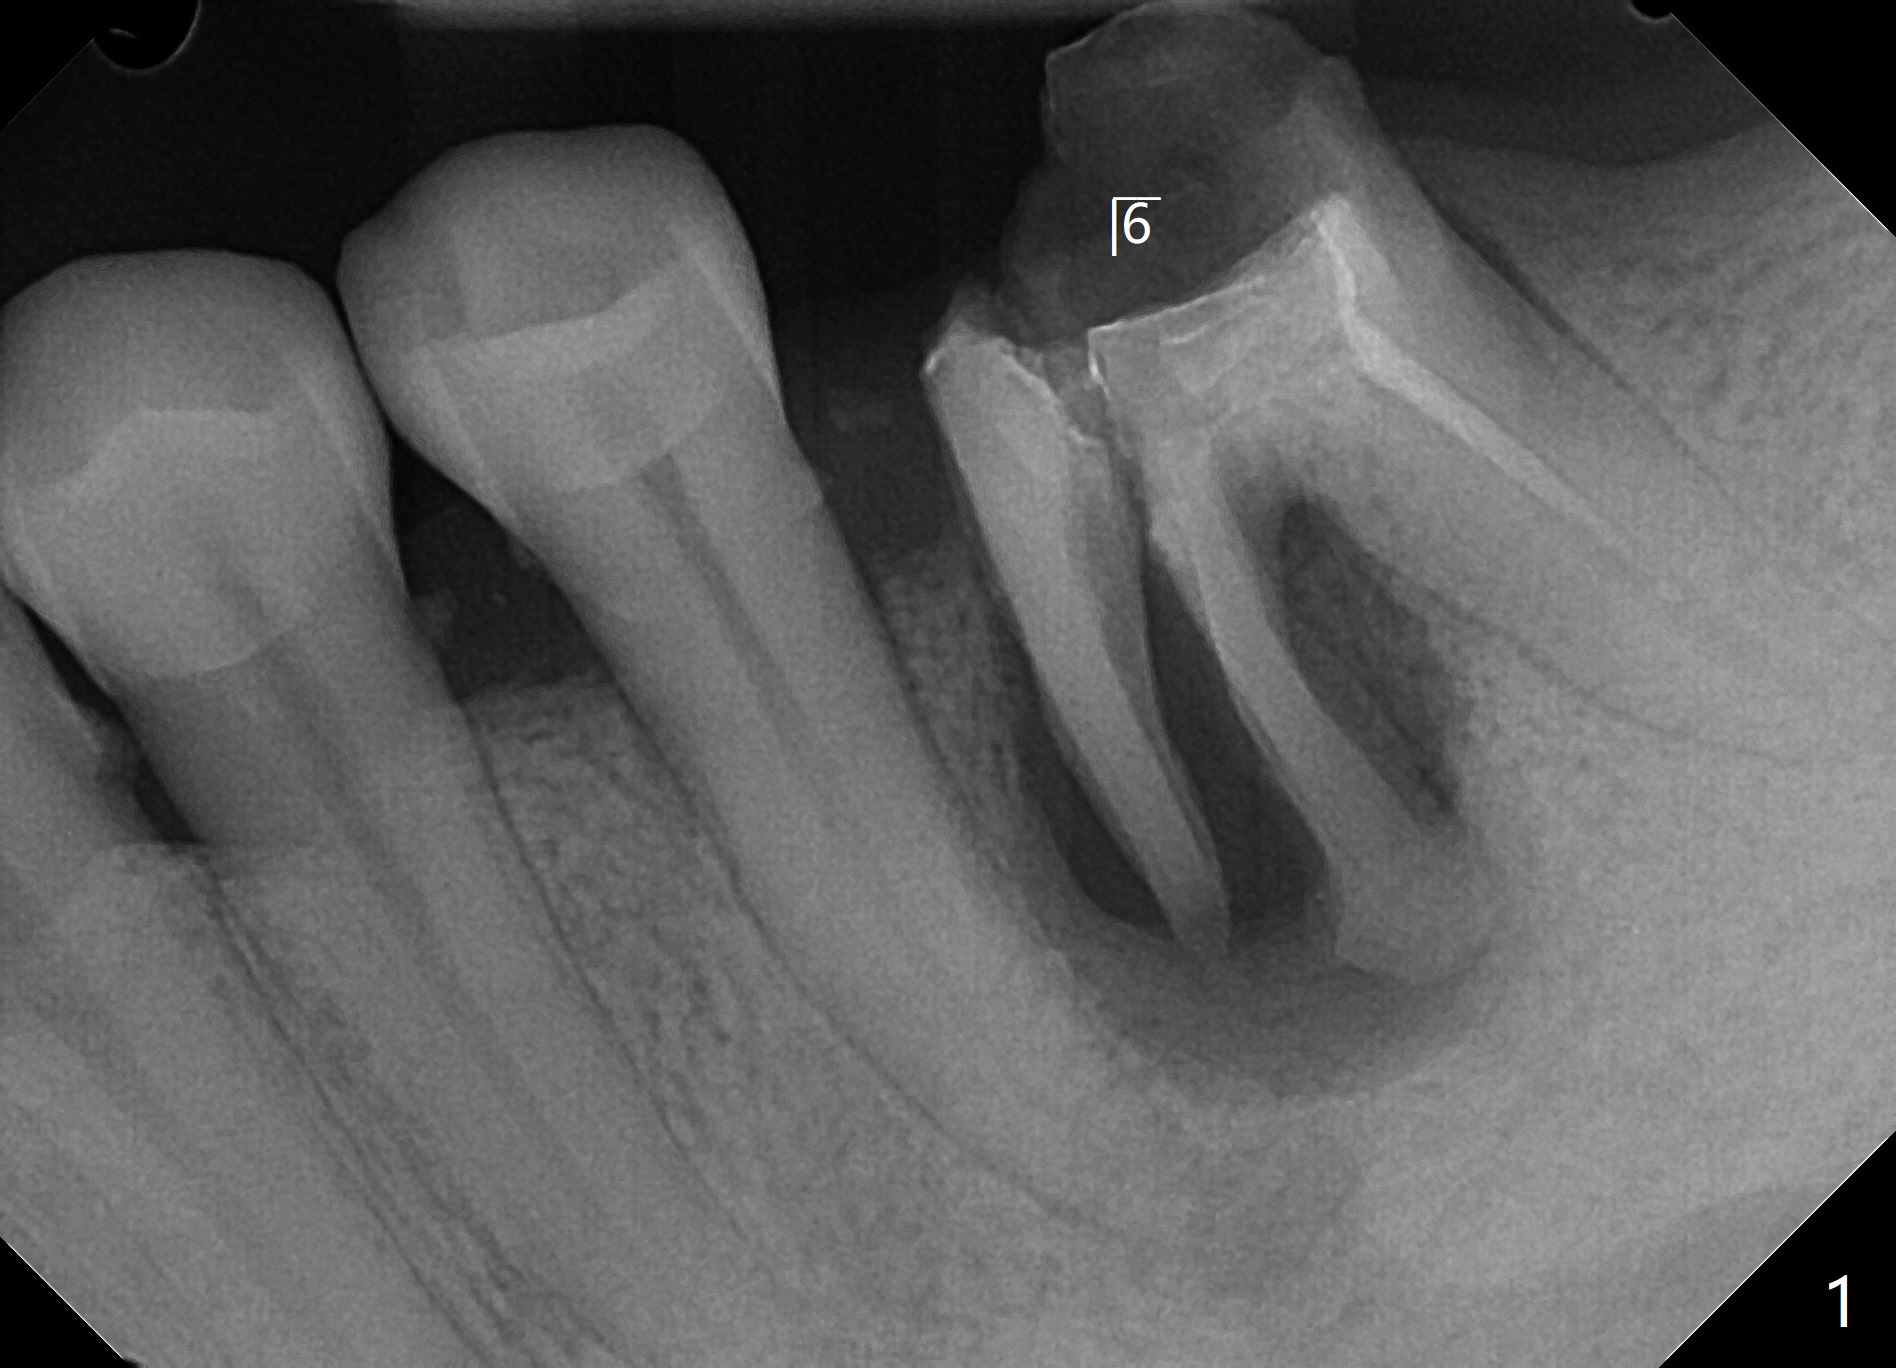

49岁男半年前要求粘固左下6牙冠,近中根纵裂,与7缺失有关,前磨牙牙根特别长,说明咬合力大,也是纵裂原因。